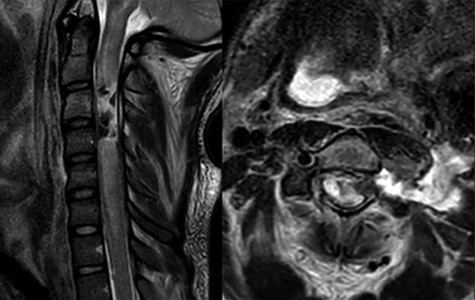

A 24-year-old African–American male presented with a gunshot wound through the left face and neck. On exam the patient was noted to be pulseless and apneic. After resuscitation, initiation of a mass transfusion protocol and return of spontaneous circulation, the patient was GCS 11 (E4V1TM6) and was noted to have no movement in any extremities. A computed tomographic (CT) cervical spine scan and CT angiography of the neck revealed a bullet trajectory through the left C2–3 facet with fractured c3 posterior elements and a bullet fragment at the C3 level, a left vertebral artery dissection, and left internal and external carotid artery transections (Fig. 1). The patient underwent an emergent tracheostomy, neck exploration, left ICA/ECA ligation and partial wound closure. This was followed by endovascular embolization of the left vertebral artery. The patient was noted to have serosanginous drainage from the neck wound consistent with a CSF leak. After an unsuccessful trail of conservative management, a lumbar drain was placed and confirmed with fluoroscopic guidance without CSF egress. A magnetic resonance imaging (MRI) scan of the cervical spine was obtained which demonstrated a pronounced CSF fistula and a complete obstruction of the CSF space at the C3–6 levels (Fig. 2).

MRI T2 weighted sequence sagittal (left) and axial (right) at the c3 level demonstrates severe spinal cord damage, canal obliteration from c3 to c6 and a large left sided csf fistula at the C3 level.

In the first case presented, surgical exploration for stabilization and CSF leak repair was offered, but the patient declined, the patient then underwent CSF diversion with a lumbar drain which was ultimately unsuccessful due to a physiologic myelographic block from c3 to c6 (Fig. 2). Ultimately the csf fistula was treated successfully after placement of an EVD. In the second case, there was a high index of suspicion of a csf block at the level of injury and a lumbar drain was not placed. The patient was successfully treated with CSF diversion through EVD for 7 days.